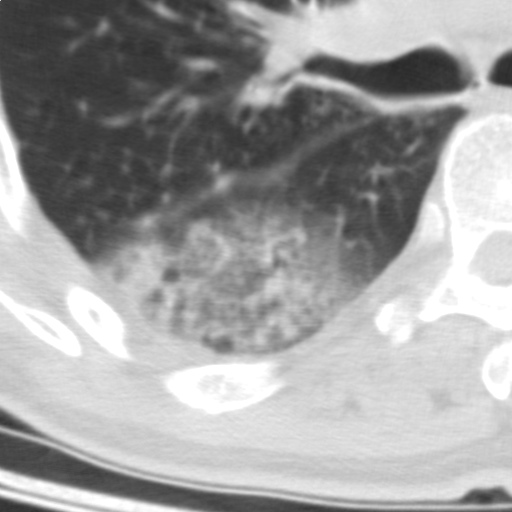

以下是引用随光逐影在2009-5-1 13:53:00的发言:[br]考虑为:1)两肺血行播散型肺结核;2)右肺下叶炎症感染。3)右侧胸膜增厚。